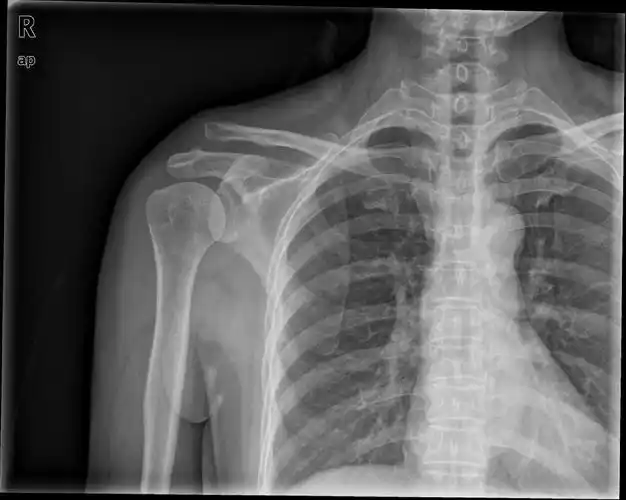

锁骨骨折及肩锁脱位的术后康复_锁骨骨折_治疗方式_康复锻炼 - 好大夫